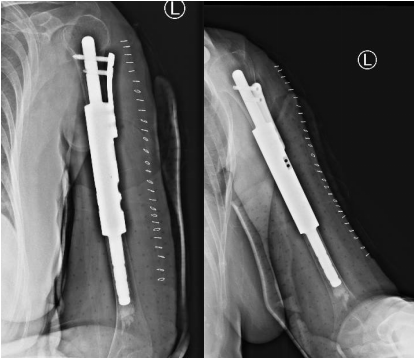

??患者术后影像学检查

??最终,曹学军顺利为刘阿姨完成了手术,术中病理结果提示肿瘤切缘干净。术后3天,刘阿姨就可以慢慢开始进行功能锻炼了。术后一周,患肢的疼痛基本消失,功能也恢复了80%以上。近期,刘阿姨进行了术后的复查,复查结果显示肿瘤未见复发,假体位置良好。现在肢体功能已经恢复了90%以上,除了不能提重物以外,完全可以正常生活。